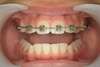

Traitement d’une occlusion inversée par l’éducation fonctionnelle

Avant